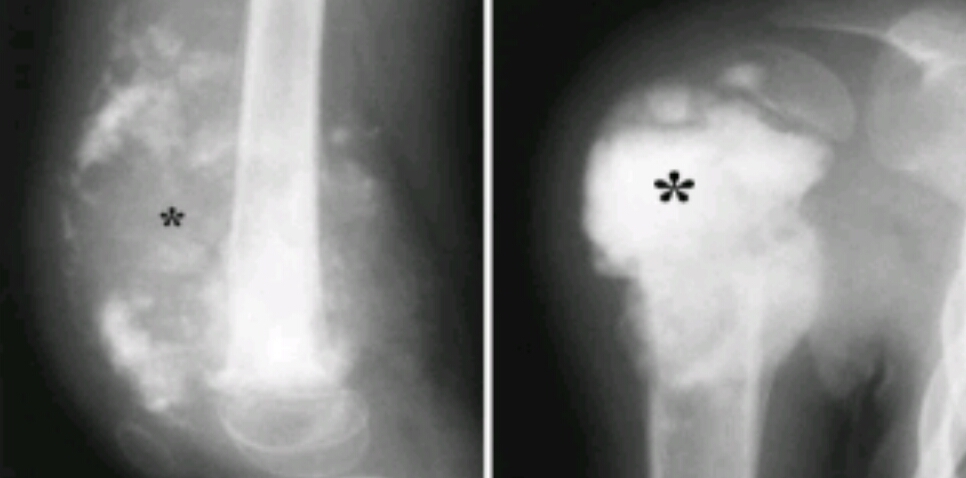

Findings? Diagnosis?

Stippled calcifications, popcorn like density, round oval area of demineralization, lytic destruction of proximal humerus

Chondrosarcoma